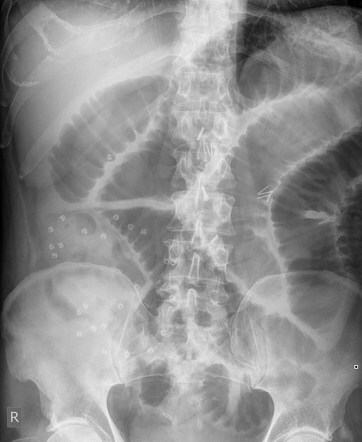

Findings on abdo x-ray of SBO

• Dilated bowel >3cm

• Central abdominal location

• Valvulae conniventes visible - complete lines crossing bowel

How well did you know this?

Abdo x-ray findings for LBO

• Dilated bowel >6cm or >9cm if caecum

• Peripheral location

• Haustral lines visible - not completely crossing bowel halfway haustra